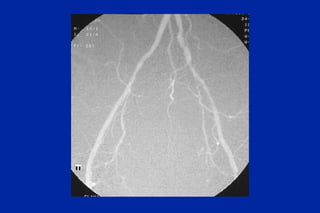

Este documento resume los principales tipos y técnicas de angiografía. Describe brevemente la angiografía, arteriografía, flebografía y linfografía, así como las técnicas de contraste y materiales utilizados. También explica los principales accesos vasculares, la técnica de Seldinger, la angiografía por sustracción digital y algunas técnicas endovasculares comunes.